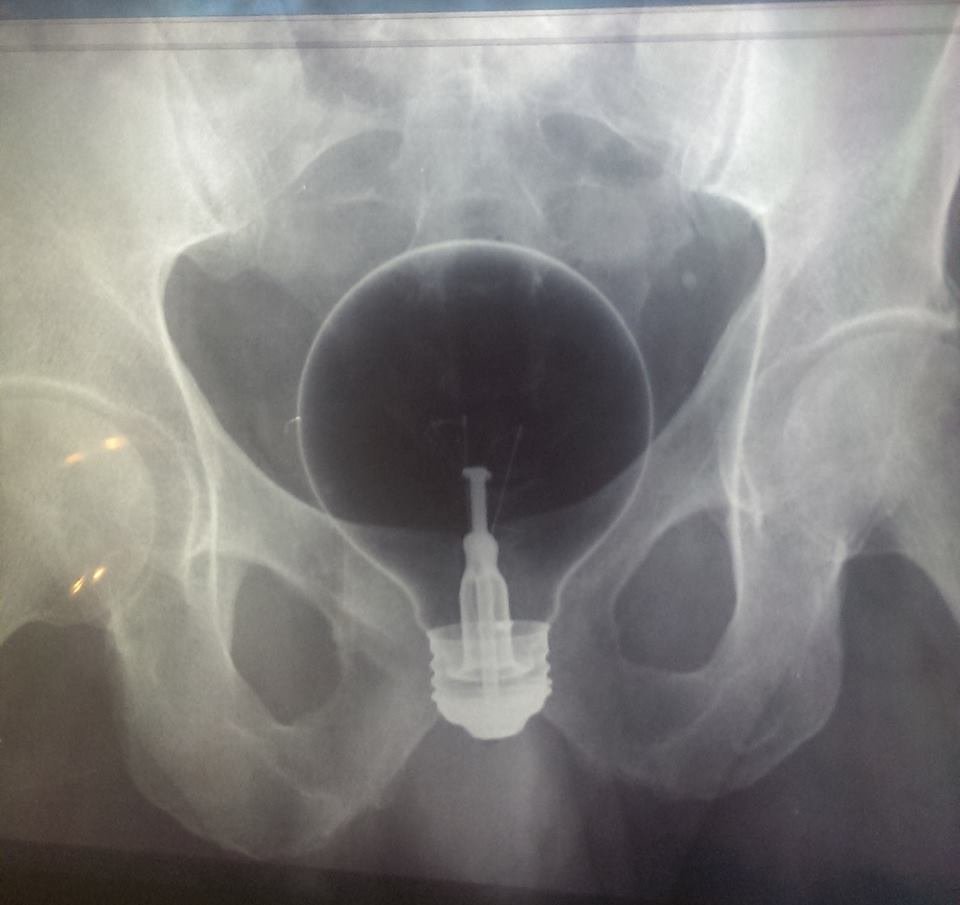

Lâmpada:

Esse foi difícil de engolir e de retirar, e pra piorar a lâmpada é muito resistente, deu uma trabalheira.